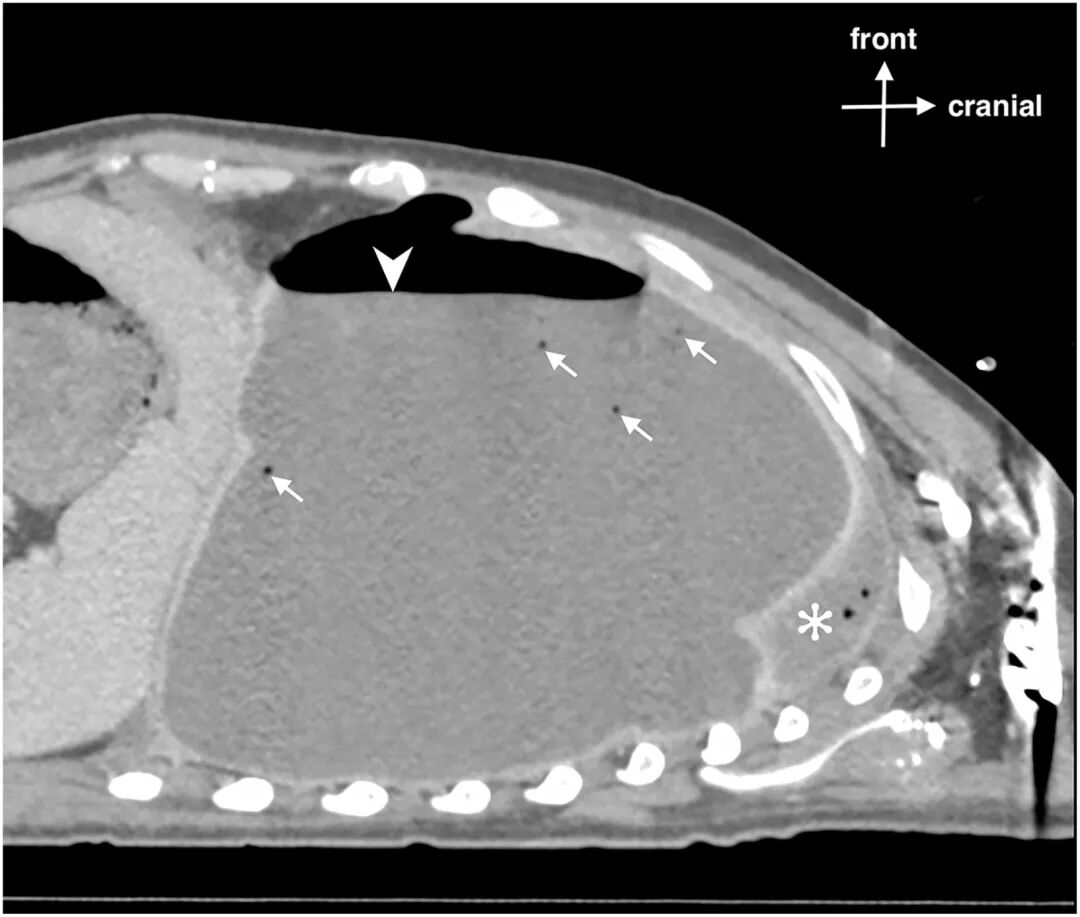

行床旁超声(图1)显示左侧大量胸腔积液,可见浮游物,且肺滑动征消失。计算机断层扫描(CT)证实左侧广泛脓气胸伴纵隔移位(图2)。

图2:胸部增强CT矢状位重建图像

图1超声显示气胸时平流层征(条形码征)。由于肺滑动征消失,M型超声图像全程表现为均匀的水平线(正常沙滩征模式消失)。胸膜线显示为清晰的高回声水平线。在B型图像右侧可见低回声胸腔积液(箭头)及游离气体(三角箭头),符合脓气胸表现。肺滑动征消失同时合并可见胸腔积液提示复杂胸膜病变。图2显示左侧大量胸腔积液,并可见气液平面(三角箭头),提示胸膜腔内存在游离气体。非重力依赖性游离气体(箭头)在积液最上方形成清晰、光滑的气液界面,符合液气胸(胸腔积液合并气体蓄积)表现。塌陷的左肺向上受压(星号)。上述表现符合脓气胸伴大量胸腔积液。